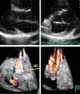

Stitch abscess

An abscess is a collection of pus that has built up within the tissue of the body. Signs and symptoms of abscesses include redness, pain, warmth, and swelling. [Source: Wikipedia ]